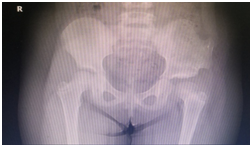

第二次术前